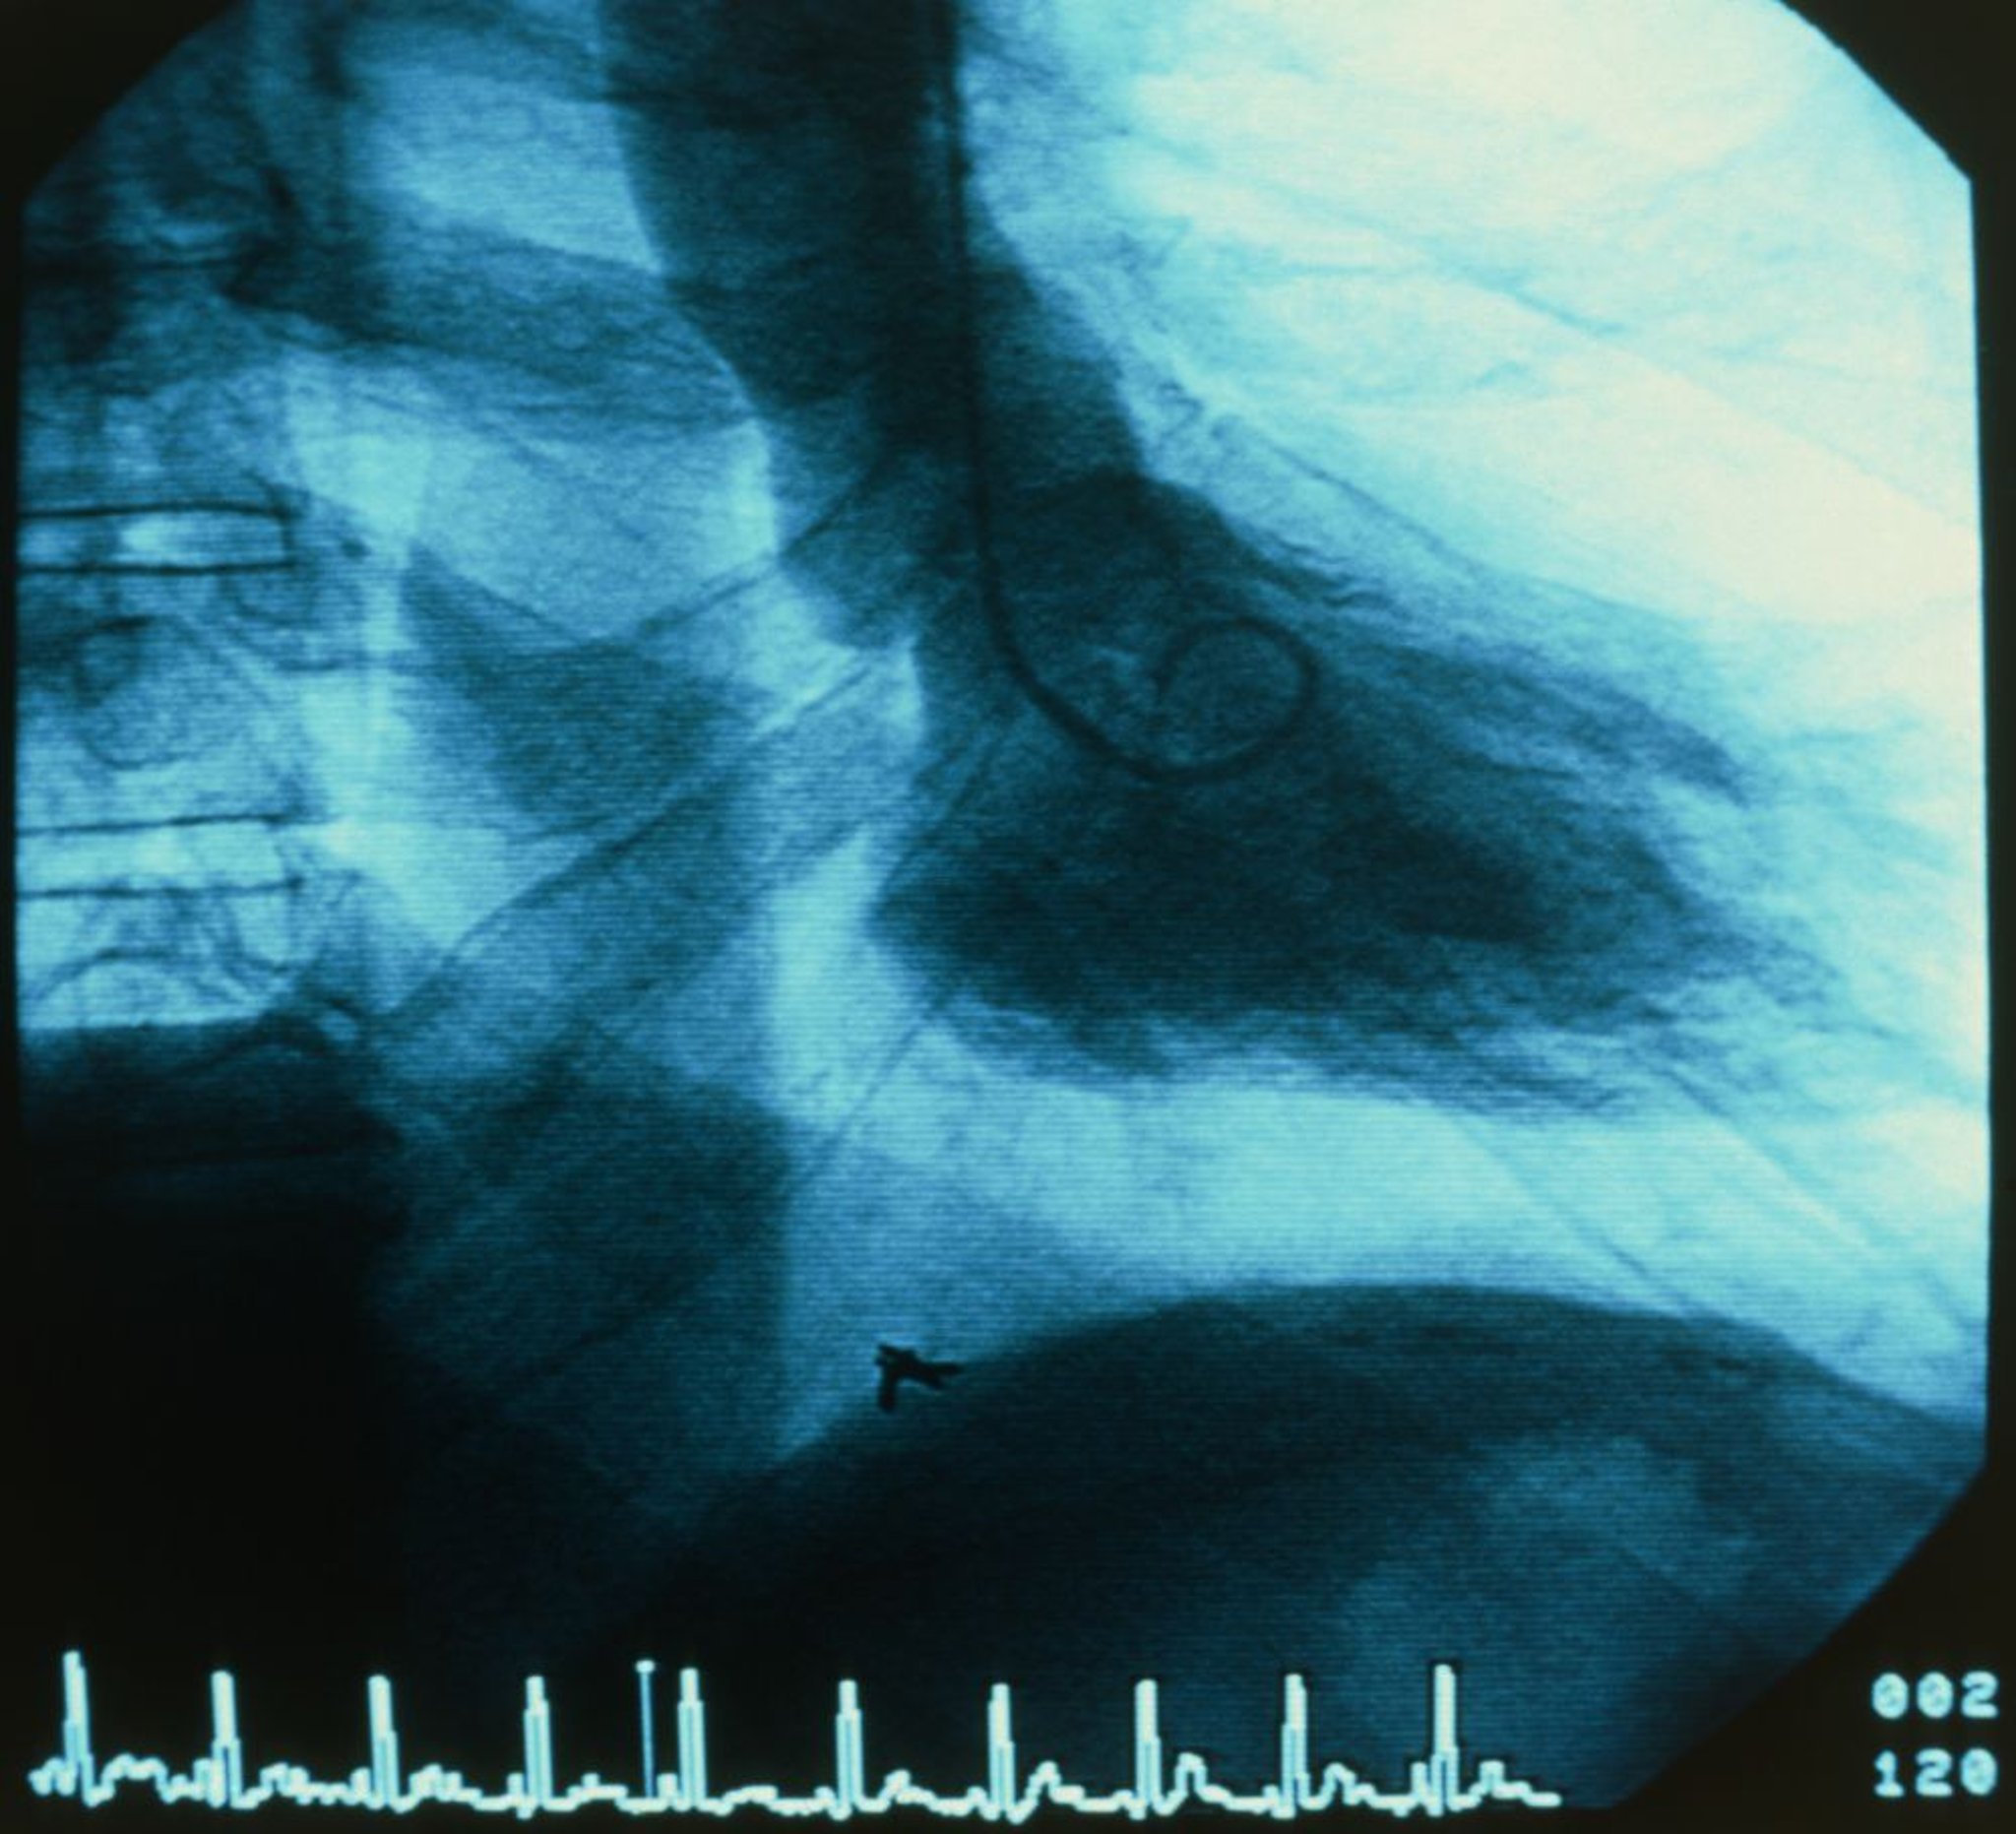

Injection of radiopaque contrast agent into coronary or pulmonary arteries, the aorta, and cardiac chambers is useful in certain circumstances. Digital subtraction angiography is used for nonmoving arteries and for chamber cineangiography.

Coronary angiography via left heart catheterization is used to evaluate coronary artery anatomy in various clinical situations, as in patients with suspected coronary atherosclerotic or congenital disease, valvular disorders before valvular replacement, or unexplained heart failure.

Aortic angiography via left heart catheterization is used to assess aortic regurgitation, coarctation, patent ductus arteriosus, and dissection.

Ventriculography is used to visualize ventricular wall motion and ventricular outflow tracts, including subvalvular, valvular, and supravalvular regions. It is also used to estimate severity of mitral valve regurgitation and determine its pathophysiology. After left ventricular mass and volume are determined from single planar or biplanar ventricular angiograms, end-systolic and end-diastolic volumes and ejection fraction can be calculated.

Coronary angiography shows the presence and degree of stenosis but not the functional significance of the lesion (ie, how much blood flows across the stenosis) or whether a specific lesion is likely to be the cause of symptoms.